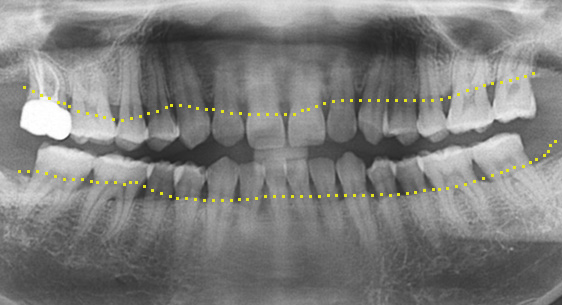

치조골 손상이 심해 발치를 하고 임플란트를 해야 하는 상황

인접치아로 발치된 공간을 메움

자연치보존 교정치료